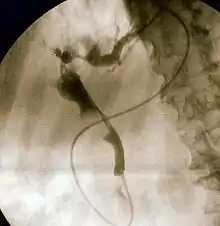

Ретроградная холангиопанкреатография (РХПГ) (англ. Endoscopic retrograde cholangiopancreatography (ERCP)) — метод, комбинирующий эндоскопию с одновременным рентгеноскопическим обследованием. Эндоскоп вводится в двенадцатиперстную кишку к большому дуоденальному сосочку, устье которого открывается в просвет двенадцатиперстной кишки. Через канал эндоскопа протягивается зонд с внутренним каналом для подачи контрастного вещества на конце которого расположена (сделанная из более плотного пластика) канюля, которую врач проталкивает в устье сосочка в жёлчные и панкреатический протоки вводится рентгеноконтрастное вещество. Затем с помощью рентгеновской аппаратуры получается изображение протоков. Метод был впервые использован в 1968 году.

Проведение обследования. Эндоскопическая «ретроградная холангиопанкреатография» (РХПГ, ЭРХПГ) выполняется только в условиях стационара. Перед исследованием всегда делается успокоительный укол. После местной анестезии глотки специальный оптический прибор (дуоденофиброскоп) проводится через рот, пищевод и желудок в двенадцатиперстную кишку к тому месту, где общий жёлчный проток и проток поджелудочной железы, соединяясь между собой, образуют ампулу большого дуоденального сосочка, устье которого открывается в просвет двенадцатиперстной кишки. С помощью специальной трубки, проведённой по каналу эндоскопа через устье сосочка в жёлчные протоки и в проток поджелудочной железы вводится рентгеноконтрастное вещество. Затем с помощью рентгеновской аппаратуры получается изображение протоковой системы. При обнаружении сужения протока или камней в нём проводится эндоскопическая операция, которая направлена на устранение препятствия и нормальной проходимости жёлчных протоков. С этой целью с помощью различных специальных инструментов, проведённых через канал эндоскопа, проводится разрез (с помощью электрического тока высокой частоты) выходной части протока, через который извлекаются камни , .